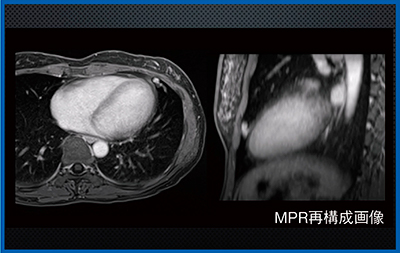

症例3は,小児の神経芽腫疑いの症例である。鎮静が必要な小児検査において,2D-FSEでは,呼吸同期を行ってもアーチファクトが生じることも多い。一方,Quick Starでは,同期なしの自由呼吸下で全身を撮像でき,脈管構造や副腎などの微細構造もしっかりと検出可能なため,CTによるスクリーニングよりも有用と考える。本症例は,Quick StarのMPR再構成画像にて右肺尖部の腫瘤(→)がはっきりと描出されており(図3),スクリーニング検査としてきわめて有用である。

図3 症例3:神経芽腫疑い(1歳6か月,男児)